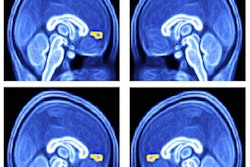

The results were interactive, 3D color-coded maps of how the brains reacted to visual, tactile, numeric, locational, violent, mental, emotional, and social meanings derived from the words.

Color-coded fMRI maps of the brain show the semantic similarities during listening (top) and reading (bottom). Images courtesy of Fatma Deniz of the University of California, Berkeley.The researchers suggested the maps could be used clinically to compare language processing in healthy people against those with stroke, epilepsy, and brain injuries that impair speech and tailor the most appropriate treatment for their needs.